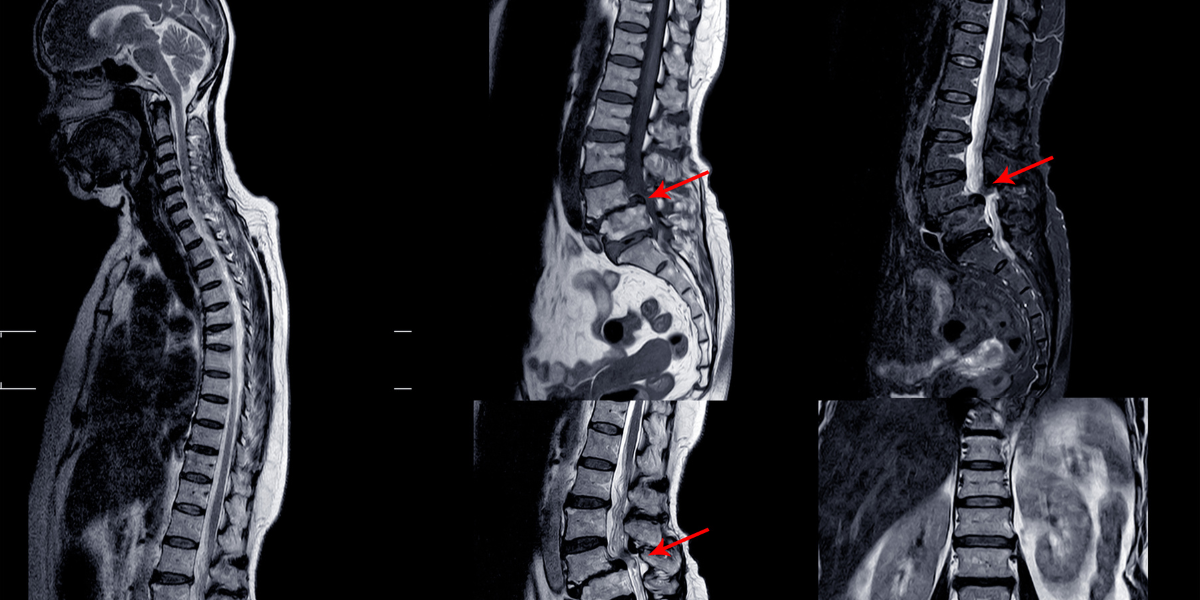

Cervical myelopathy refers to a condition where the spinal cord in the neck becomes compressed, leading to neurological impairments. Common causes include disc herniation, degenerative changes, spinal stenosis, or spinal cord injury.

Symptoms may include neck stiffness, pain, weakness or numbness in the arms or legs, tightness of both lower limbs and difficulty with coordination and balance. Diagnosis typically involves an MRI to detect spinal cord compression. Treatment options range from non-surgical methods to surgical intervention, depending on the severity and progression of symptoms.